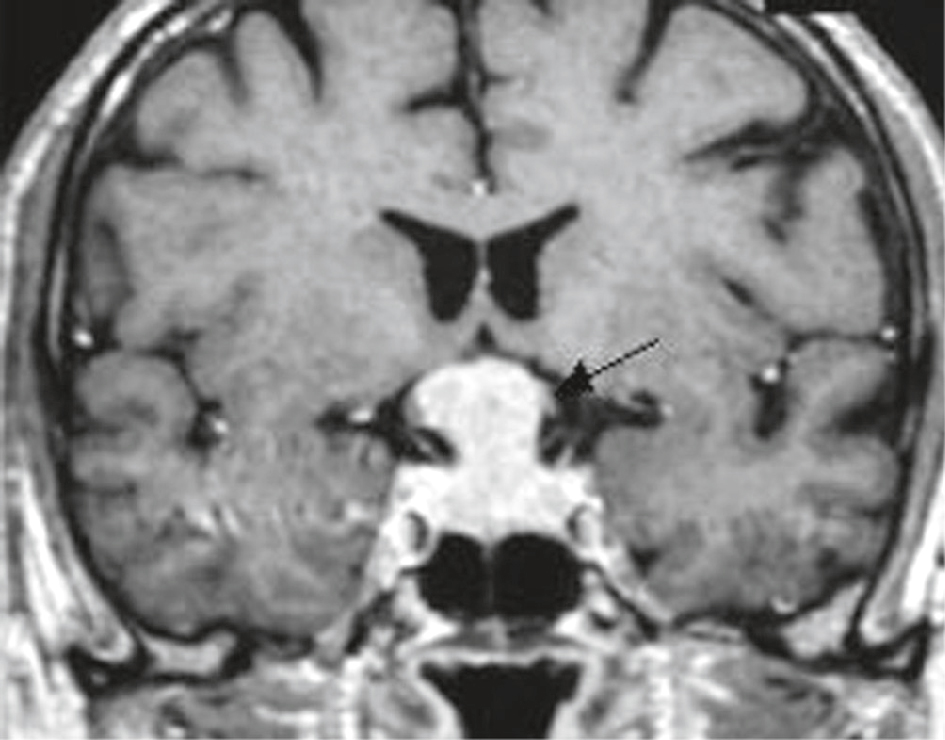

IRM cérébrale chez une femme de 57 ans avec hémianopsie bitemporale. Séquence T1 après injection dans le plan coronal : lésion à développement intrasellaire et à extension supra-sellaire, en forme de « bonhomme de neige » ou de « 8 » (forme liée à la constriction du diaphragme sellaire), prenant le contraste de manière homogène. La tige pituitaire n’est plus visible. Important refoulement du chiasma optique (flèche). Pas d’envahissement des loges caverneuses.

Image en coupe coronale d’une IRM cérébrale montrant une patiente de 57 ans présentant une hémianopsie bitemporale, dans un contexte évocateur d’une atteinte du chiasma optique. On observe une masse isointense en hypersignal T1 située juste au-dessus de la selle turcique, compriment la région chiasmatique. La flèche indique précisément la zone de compression à l’origine probable du déficit visuel bilatéral temporal. La morphologie des ventricules latéraux reste conservée, sans signe d’hydrocéphalie associée. L’ensemble de l’architecture cérébrale reste globalement symétrique, en dehors de cette lésion sellarienne typiquement compatible avec un adénome hypophysaire comprimant le chiasma optique.